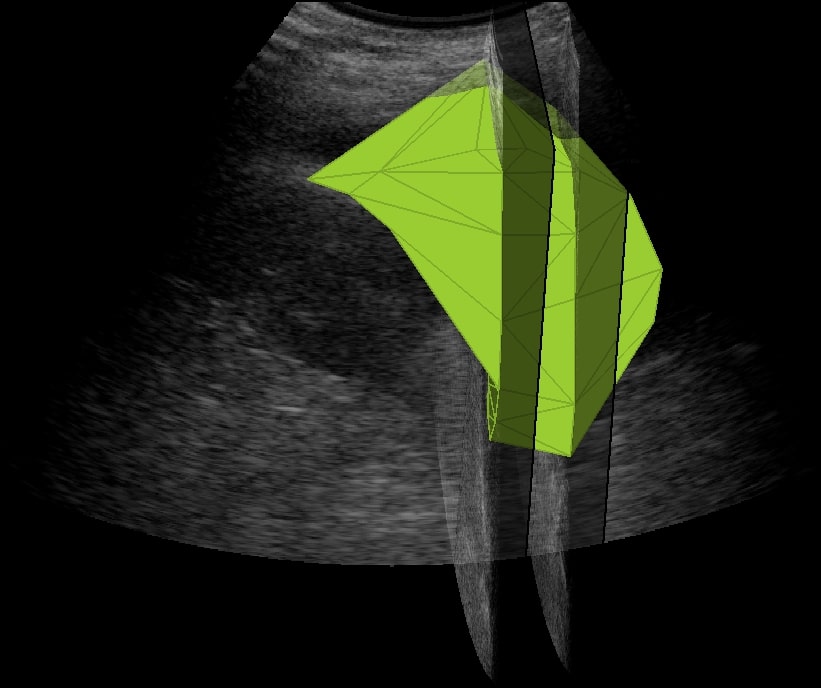

La quantificazione accurata del versamento pleurico è cruciale per una gestione tempestiva ed efficace dei pazienti critici, specialmente in contesti di emergenza come pronto soccorso e unità mobili. Questo studio preliminare valuta l’impiego di un algoritmo di segmentazione basato su deep learning per l’analisi volumetrica del versamento pleurico da immagini ecografiche polmonari, acquisite sia in ambito ospedaliero che pre-ospedaliero.

L’algoritmo di segmentazione si basa su una ResNet modificata, addestrata su immagini ecografiche acquisite nello stesso contesto clinico e segmentate manualmente da due operatori esperti. Le segmentazioni automatiche sono state confrontate in blind con quelle manuali. Dai contorni segmentati è stato ricostruito il volume del versamento pleurico (in cm³) mediante integrazione dell’area su sequenze longitudinali e trasversali. I volumi stimati sono stati confrontati con quelli drenati tramite toracentesi, considerata gold standard. Le performance dell’algoritmo di segmentazione sono state valutate con Dice Similarity Coefficient (DSC), mentre l’attendibilità della stima del volume del versamento con Mean Absolute Error (MAE), Root Mean Squared Error (RMSE) e coefficiente di correlazione di Pearson (r).

L’algoritmo ha mostrato buone capacità di segmentazione, con un DSC medio pari a 0.76 ± 0.05 rispetto agli operatori umani. L’analisi inter-operatore ha mostrato una concordanza simile (DSC 0.78 ± 0.04), confermando l’affidabilità del modello. Il volume stimato ha mostrato un MAE medio di 42.4 ± 19.6 cm³ e un RMSE di 45.5 cm³ rispetto al volume drenato. Il coefficiente di correlazione tra stima automatica e gold standard è risultato elevato (r = 0.84, p < 0.001). Il tempo medio di elaborazione per paziente è stato inferiore a 3 secondi. Questo studio preliminare dimostra la fattibilità e robustezza dell’utilizzo di algoritmi di deep learning per la segmentazione e quantificazione automatizzata del versamento pleurico a partire da ecografia polmonare. I risultati supportano la prosecuzione dello studio su scala più ampia, con l’obiettivo di integrare tali strumenti nella pratica clinica, migliorando la rapidità decisionale e riducendo l’invasività diagnostica.